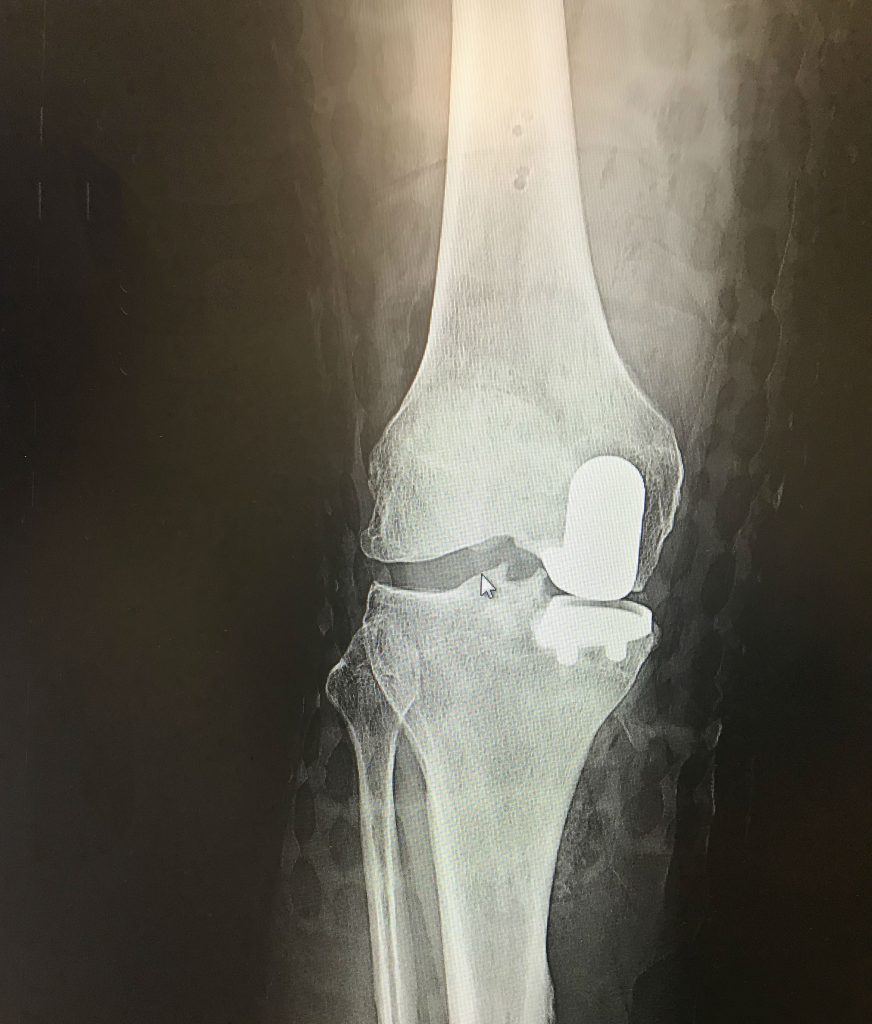

In college I had blown out my ACL. My doctor at the time only cleaned up the injury, but did not repair the ACL. I had continued to be active and even took up running and completed the NYC Marathon. Unfortunately, I had a lot of movement in the knee and this caused my cartilage to deteriorate over the next 30 years. By the time I finally consulted with Dr. DiFelice, he could see a pretty decent amount of bowleggedness due to deteriorated cartilage. He recommended a partial knee replacement and he would try to clean up my damaged ACL. I had the surgery on September 28th. Dr. DiFelice indicated the surgery went well and he was able to tighten up the ACL so my knee would be more stable. I did outpatient physical therapy, bought a Peloton bike and continued at home. I assumed I would have to write off the ski season, but at my December follow up appointment I got the great news that all looked good and I could snowboard! I got in five days with no issues. While I'm not hitting the parks I am able to keep up with friends on black diamond runs! I have had no pain in the knee even though I have snowboarded and become an avid cyclist (including a 41 mile outdoor ride five months post surgery)!